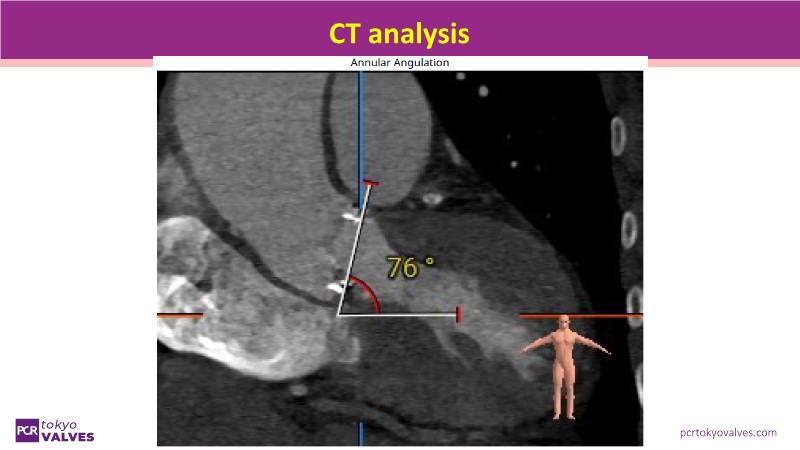

Watch this expert-led session on the latest Evolut TAVI advancements, device selection for small annulus cases, and strategies for complex anatomies. Learn about redo-TAVI feasibility and key 1-year data from the SMART trial.

• To master implantation techniques and discern the latest technological evolutions for treating patients with complex anatomies